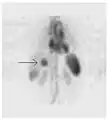

A nuclear medicine SPECT liver scan with technetium-99m labeled autologous red blood cells. A focus of high uptake (arrow) in the liver is consistent with a hemangioma.